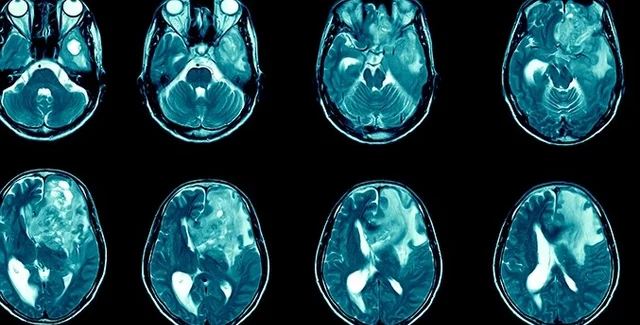

Глиобластома в головном мозге человека | Фото: Getty Images Plus

Глиобластома является одной из наиболее распространенных и агрессивных форм рака головного мозга. При этом она чрезвычайно трудно поддается лечению. К счастью, исследователи полагают, что им, возможно, удалось найти способ борьбы с этим типом рака, пишет Science Alert.